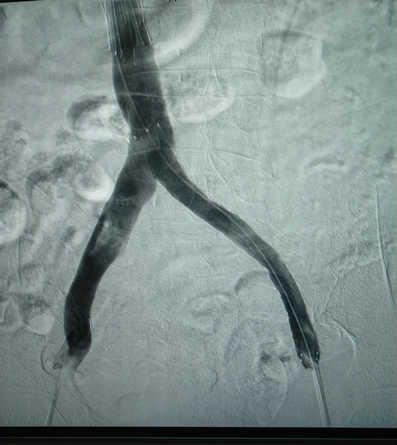

6月30日晚8时,在刘亚民教授的精心指导下,介入科李渊博主治医师与科室医护人员为该患者实施了血管开通、球囊扩张成形及支架置入术,术后造影,左侧髂静脉通畅,患者安全返回病房。

血管开通、球囊扩张成形及支架置入术在我院是第一例,也宝鸡地区县级医院开展的第一例手术,原来只能在三甲医院开展的手术,现在在家门口就能够实施,为广大患者提供了便利、节省了费用,也标志着我院在血管疾病诊治方面又迈出了新的一步。